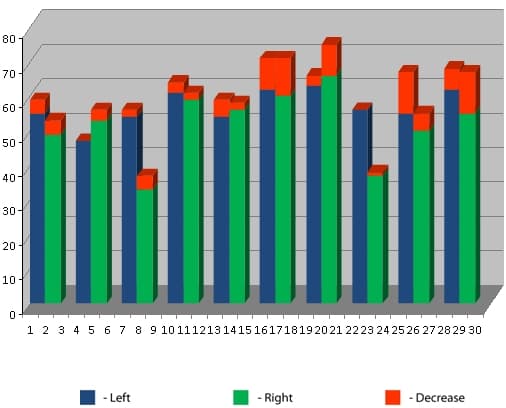

In another test group, the Voll method was employed to assess functional activity using a Mini-Expert-DT electroacupuncture diagnostic apparatus.

The initial measurements demonstrated that the test group was on average uniform in terms of the functional activity of organs and body systems, because the total deviation of the electric potential from the norm did not exceed 16+1.3%. The normal range of electric potential values lies between 50-60 standard units.

As Figure 2 illustrates, the activity of the majority of the organs and systems falls in the normal range before the mobile phone conversation.

Figure 3 shows a dramatic reduction in the activity of body systems such as the immune, endocrine, circulatory, and gastrointestinal systems, as a result of a 3-minute mobile phone conversation.

Figure 4 illustrates changes in the activity of organs and body systems after a three-minute phone conversation using the same mobile phone, but protected with an Aires Shield electromagnetic anomaly neutralizer. Not only are the measures restored, the are improved when compared to the baseline measurements.

Figure 5 illustrates the changes in the electric potential of the circulatory systems control points when under the influence of electromagnetic radiation from a mobile phone (second column in the diagram) in comparison with the baseline radiation (first column) and radiation with the Aires Shield (third column).

Note not only the sharp reduction in the electric potential of the circulatory system under the influence of electromagnetic radiation from the mobile phone to the level of developing progressive dystrophic changes in the system, but the obvious effect of the drop in electric potential (indicated in red), which indicates pronounced astenization and a distruption of neuroendocrinal regulation and vegetative balance.

The Aires Shield electromagnetic anomaly neutralizer both fully restores the electric potential and eliminates the progress of astenization, saving resources for the body.

The behavior of the total deviation from the electric potential norm clearly illustrates the affect of a mobile phone’s electromagnetic radiation and the Aires Shield electromagnetic anomaly neutralizer on the activity of organs and body systems. The value is 0 at the norm.

Figure 6 presents the total deviation from the electric potential norm at various stages of the experiment.

It can be seen that a three-minute mobile phone conversation reduces the activity of organs and tissues in basically healthy people by an average of 30%, which coincides with data from the WHO. People with more pronounced electric potential deviations (up to 40% from the norm), the negative affect of the mobile phone’s electromagnetic radiation is more apparent and reaches 50%, but the Aires Shield electromagnetic anomaly neutralizer not only protects the body from the affects of the man-made radiation, it also promotes restoration of the disrupted activity.

The Aires Shield stabilizes this restorative effect for several hours.